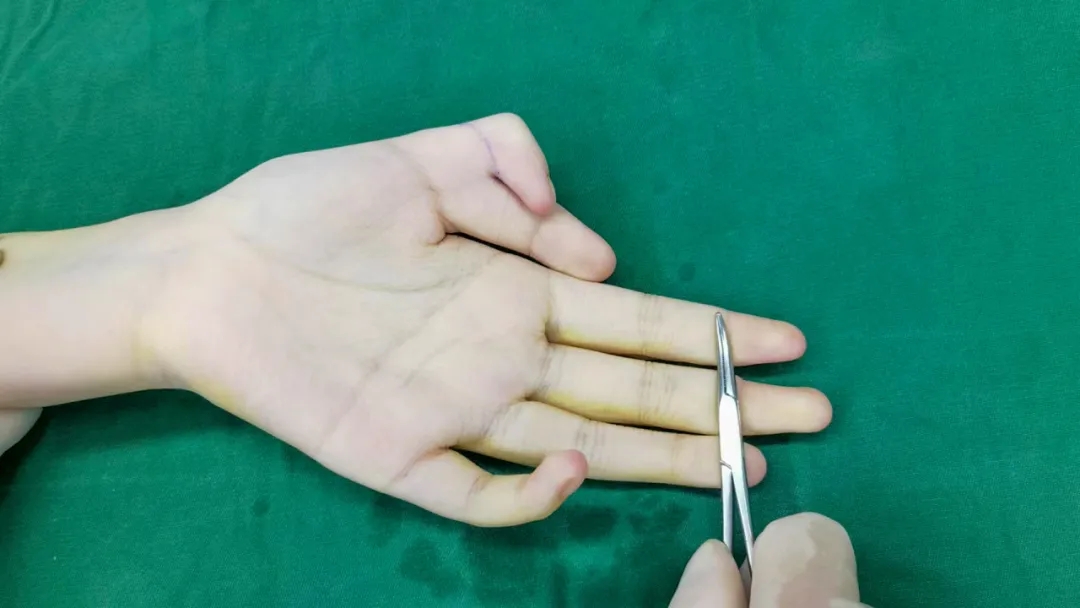

(术前)

重庆红楼医院骨科汪主任团队凭借丰富的临床经验,历时3小时,成功完成左拇指多指切除术、第一掌骨截骨矫形术、掌指关节脱位复位内固定术、拇短展肌腱止点重建术、掌指关节囊、侧副韧带修复术等手术。